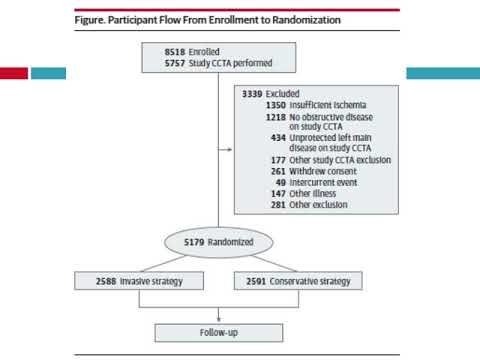

Caracteristicas basales y perfiles de riesgo de los participantes del estudio ISCHEMIA. Dra. Carolina G. Reynoso. Residencia de Cardiología. Hospital C. Argerich. Buenos Aires